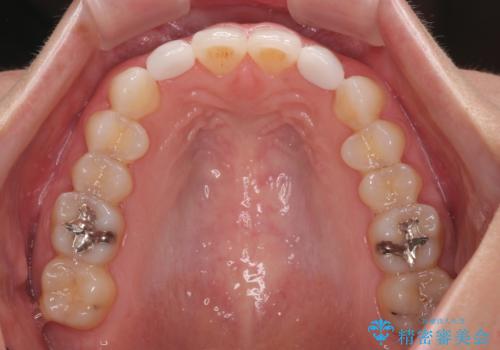

インビザラインは長時間装着を自己管理する必要がありますが、残念ながら十分な時間の装着を行うことができませんでした。

何とか矮小歯を改善するスペースを作ることはできましたが、過蓋咬合を改善するには至りませんでした。